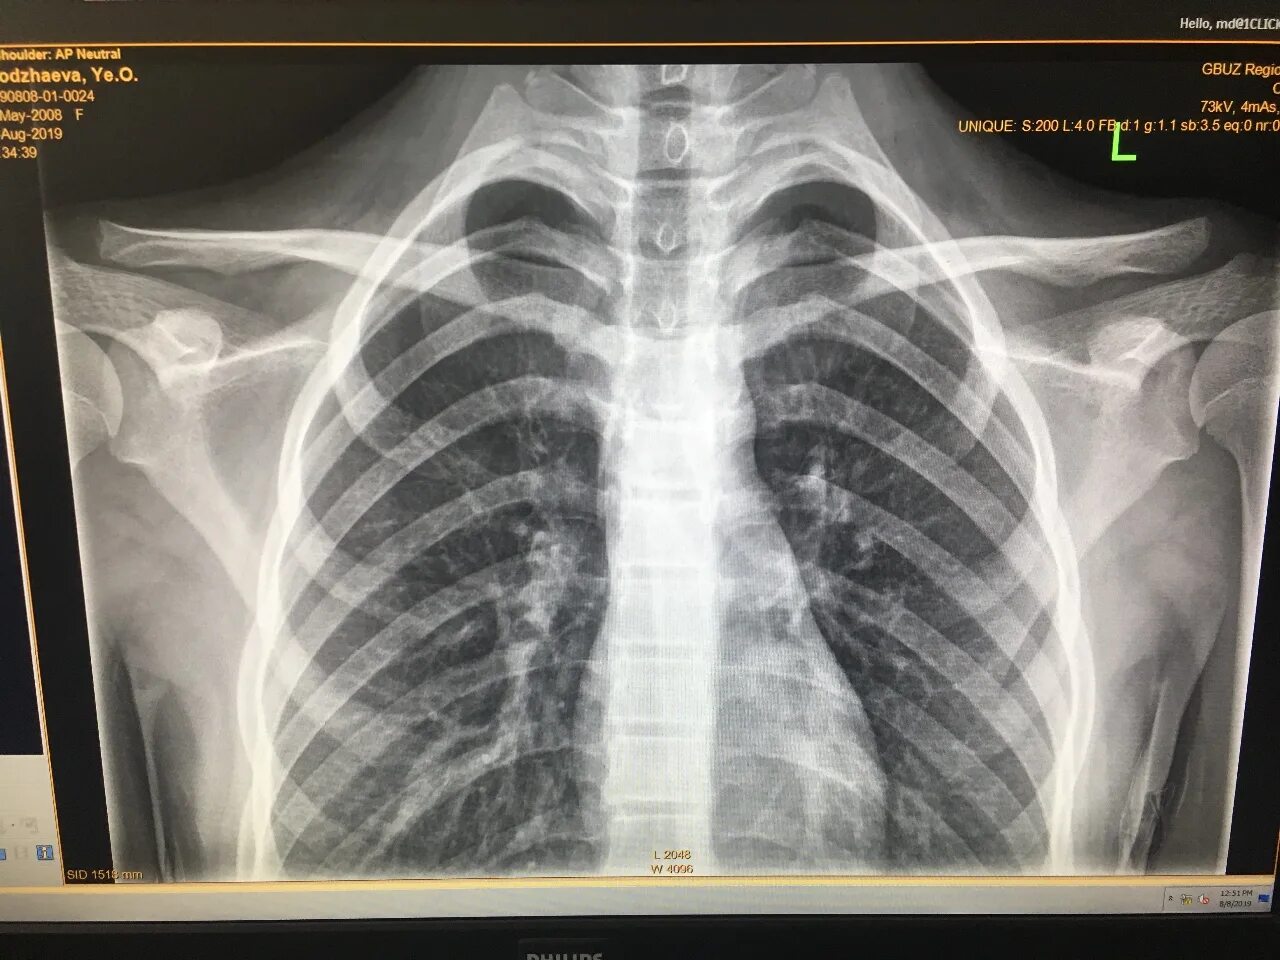

Разрыв ключично акромиального сочленения мкб 10 код